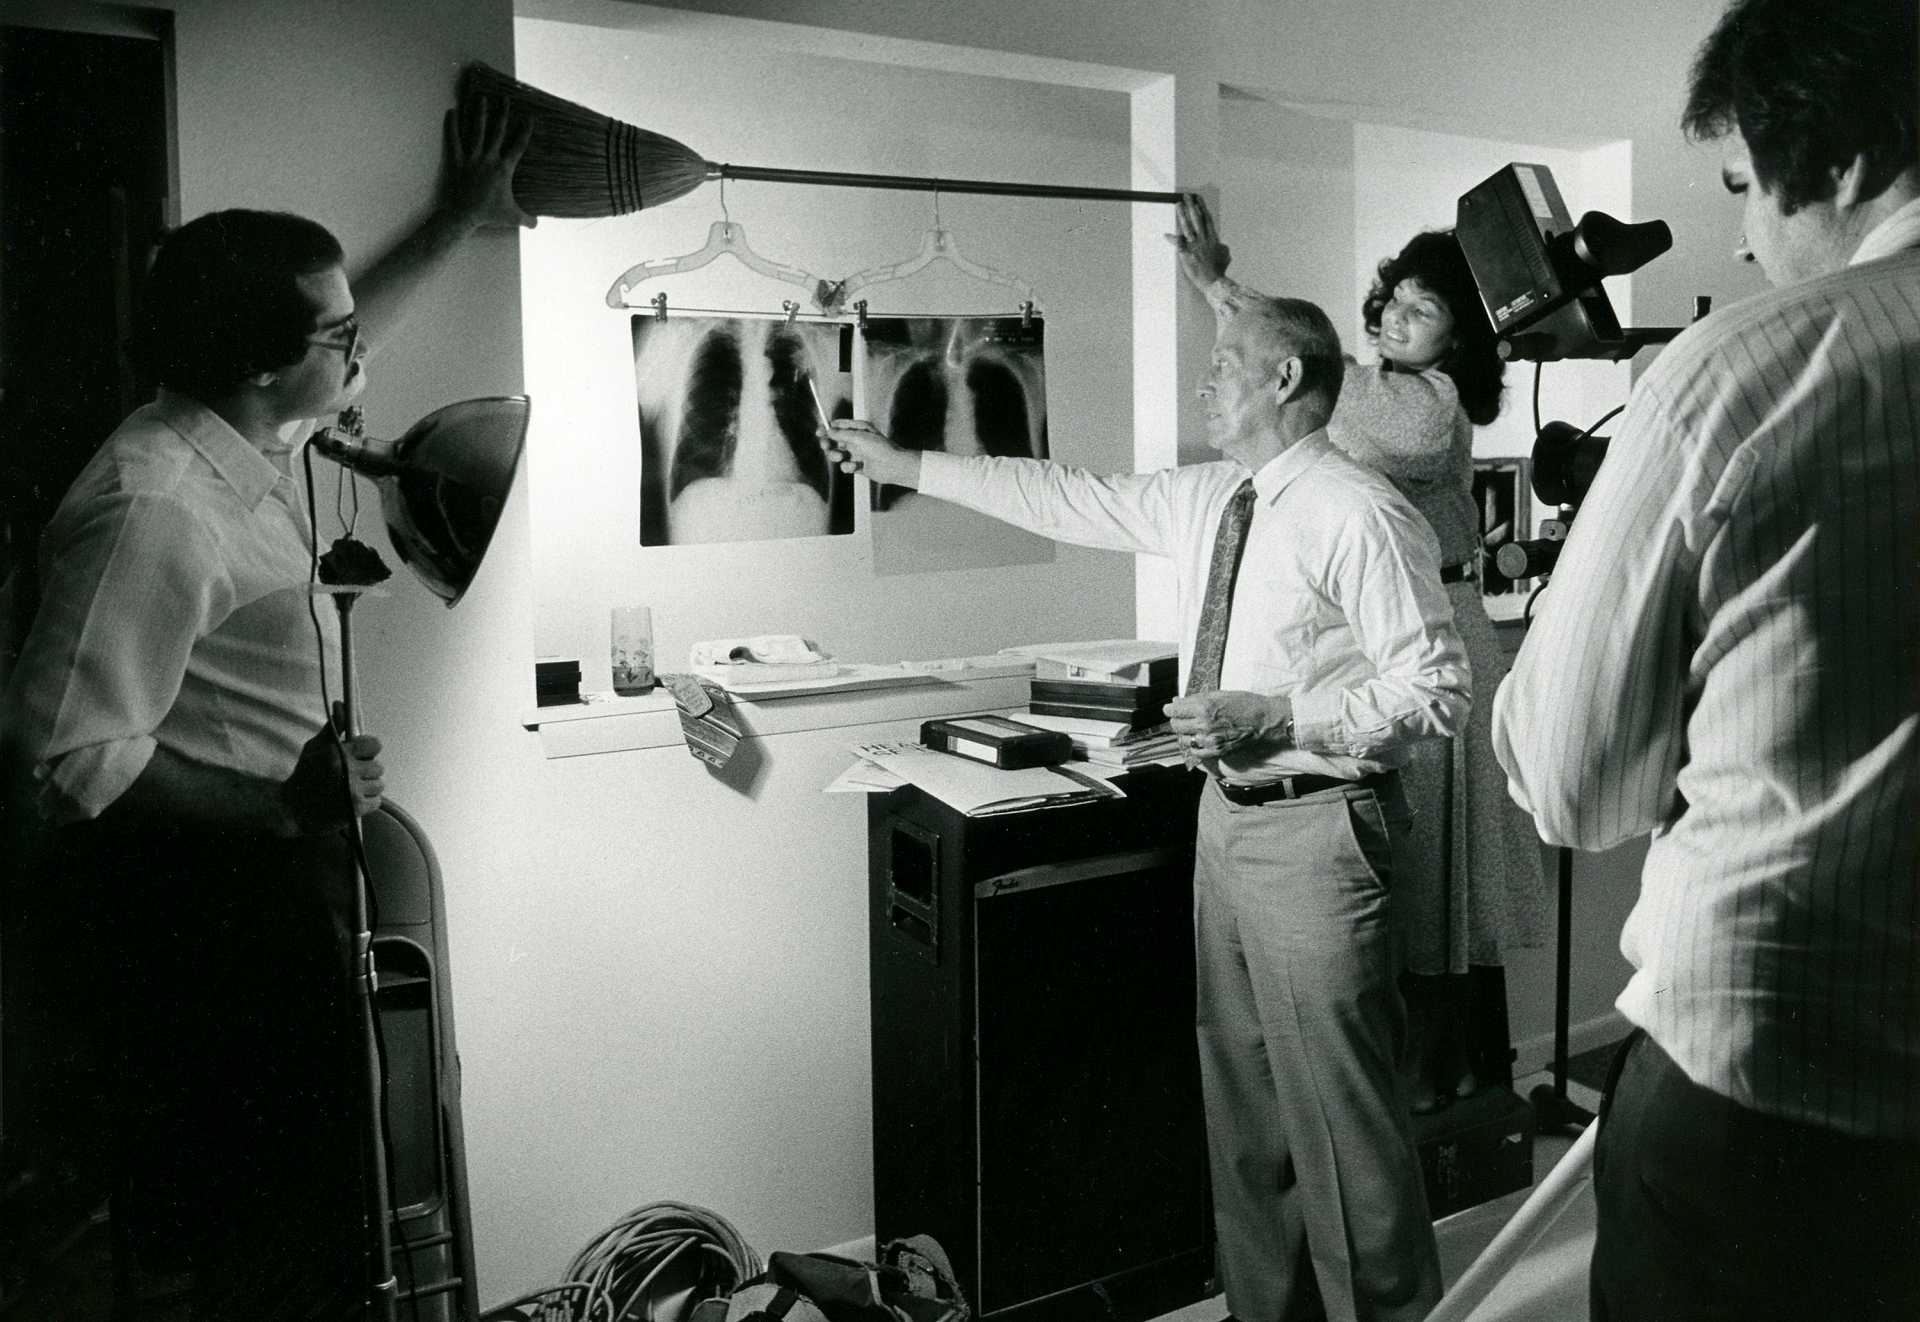

The New York Daily News dubbed her, “The hottest healer in

the East.” Singing evangelist Grace, as she became known,

was a housewife with kids and a voice to save souls when I

met her back in the spring of 1980. A gospel singer with a gift

for praying for the sick with miraculous results, Grace was

the subject of a News-Times feature article that I

photographed. The story brought her worldwide media

attention and a lifelong friend in me. In the tradition of evangelists Kathryn Kuhlman, Oral Roberts and

turn-of-the-last century tent revivalists, Grace ‘N Vessels of Christ Ministries still preaches salvation with

“signs and wonders following” as she lays hands on the sick to pray.